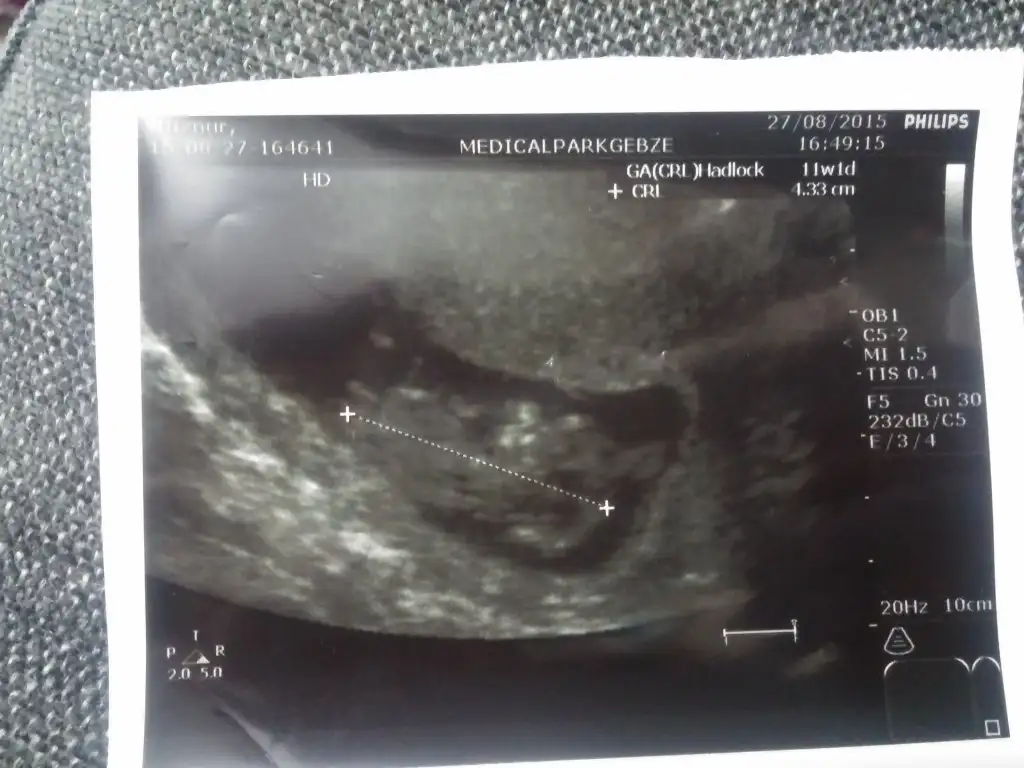

bende yeni üye oldum kızlar 13 haftalık gebeyim. doktor kız diye tahmin etti meraktan ölüyorum ne olur yardım edin

1228323-4f0e69dd96f6fc2335c12af17a1e47c8.jpg

1228324-ad64d8f262b8cdcbfd7688537388aeeb.jpg